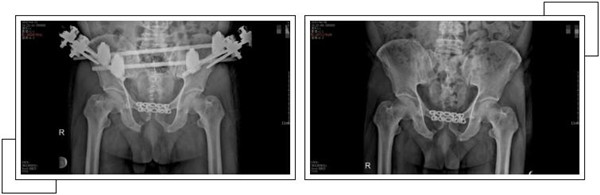

二周后,趙大叔病情穩(wěn)定,身體各方面條件符合手術(shù)指征后,骨科中心副主任羅軍帶領(lǐng)手術(shù)團(tuán)隊(duì)為其進(jìn)行了骨盆骨折、恥骨聯(lián)合分離、雙側(cè)髂骨骨折、右側(cè)恥骨上下支骨折切開(kāi)復(fù)位內(nèi)外固定術(shù),手術(shù)一個(gè)半小時(shí)順利完成。

經(jīng)過(guò)關(guān)節(jié)科全體醫(yī)護(hù)人員的精心治療和護(hù)理,術(shù)后一個(gè)月,趙大叔康復(fù)出院。出院當(dāng)天,趙大叔感謝的話說(shuō)了又說(shuō),并在來(lái)復(fù)查時(shí),特地制作了一面錦旗以表示謝意。